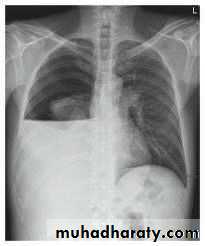

Severe dyspnea with shock